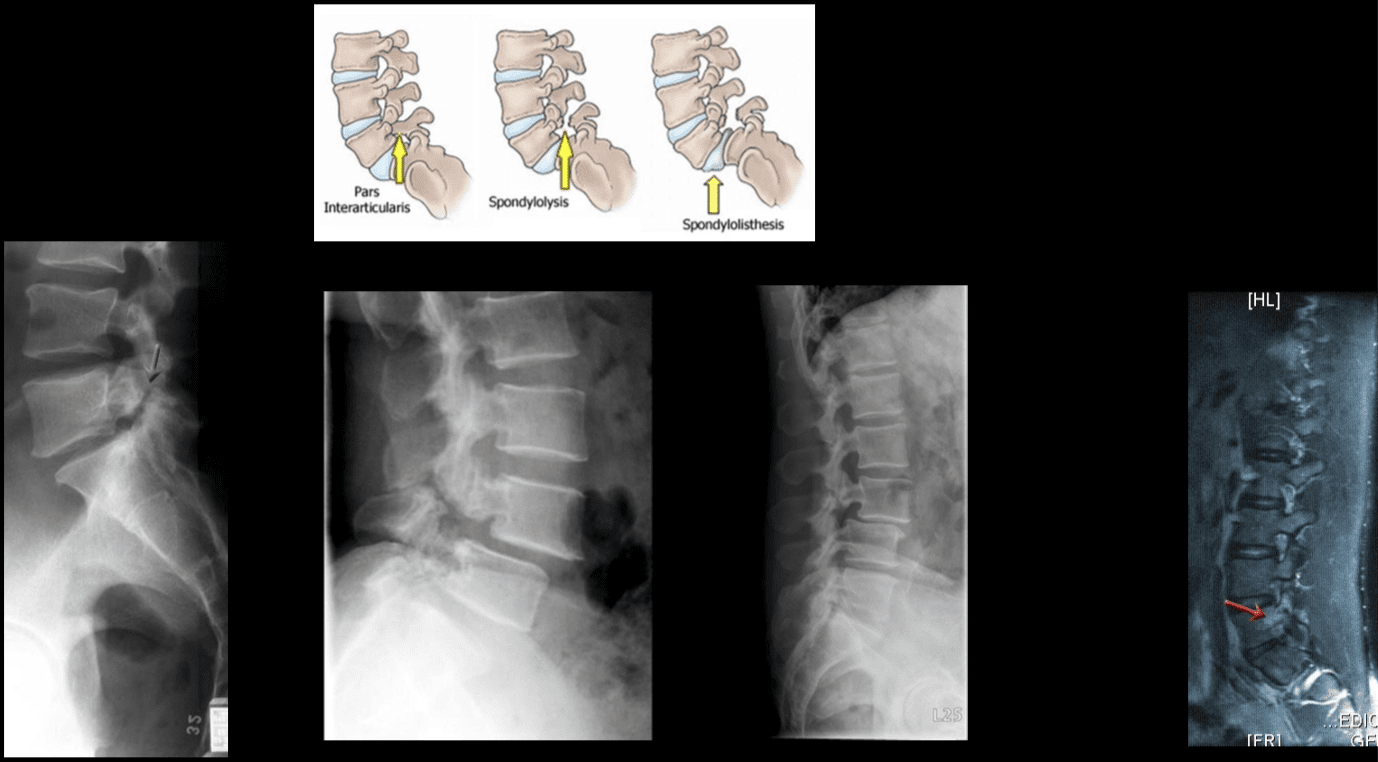

L-uġigħ u t-tenerezza lokalizzata fis-sinsla assjali ġeneralment toriġina min-nociceptors misjuba fid-diski intervertebrali, il-ġogi tal-faċċati, il-ġogi sacroiliac, id-dura tal-għeruq tan-nervituri, u l-istrutturi miofaszjali li jinsabu fl-ispina axial. Kif issemma fit-taqsimiet ta 'qabel, il-bidliet anatomiċi deġenerattivi jistgħu jirriżultaw fi tidjiq tal-kanal tas-sinsla msejjaħ stenożi spinali, żieda żejda ta' proċessi spinali msejħa osteofiti, ipertrofija tal-proċessi articulari inferjuri u superjuri, spondilolistesi, tixrid tal-ligumum flavum u herniation disk . Dawn il-bidliet jirriżultaw f'ġabra ta 'sintomi li hija magħrufa bħala claudication newroġenika. Jista 'jkun hemm sintomi bħal uġigħ fid-dahar baxx u uġigħ fir-riġlejn flimkien ma' tnemnim jew tingiż fis-saqajn, dgħjufija fil-muskoli, u qatra fis-saqajn. It-telf ta 'kontroll tal-musrana jew tal-bużżieqa jista' jissuġġerixxi l-imġieba tad-dahar tas-sinsla u hemm bżonn ta 'attenzjoni medika fil-pront biex jiġu evitati diżabilitajiet permanenti. Dawn is-sintomi jistgħu jvarjaw fis-severità u jistgħu jippreżentaw diversi estensjonijiet f'individwi differenti.

Il-marda deġenerattiva tad-diska għandha diversi dijanjosi differenzjali li għandhom jiġu kkunsidrati meta pazjent jippreżenta uġigħ fid-dahar. Dawn jinkludu; uġigħ fid-dahar idjopatiku, deġenerazzjoni tal-ġogi zygapophyseal, majelopatija, stenożi tal-ġenbejn, spondilosi, osteoartrite, u radikulopatija tal-ġenbejn. ("Marda tad-Diska Deġenerattiva" Fiżjopedja)